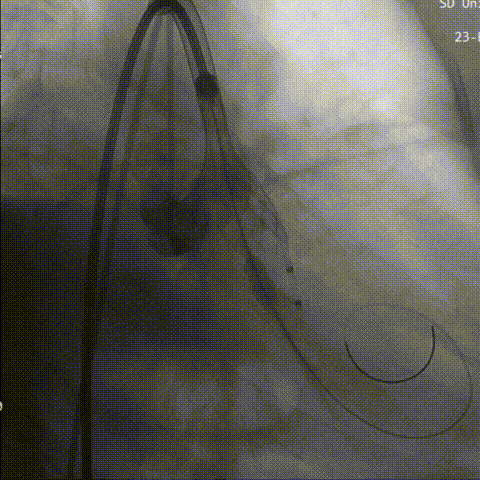

行成功跨瓣后,术者团队用23mm球囊预扩,结合瓣环及球囊预扩情况,植入预装AV26型号瓣膜。

球 囊 预 扩

初始定位

术者结合DSA影像,多角度观察瓣膜情况,在瓣膜达到一个稳定位置后,缓慢释放到工作位,造影评估显示反流明显,行第一次回收。

工作位评估

第一次回收